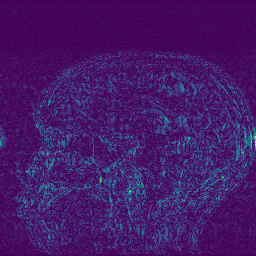

Edge preserving has always been a crucial concern in the design of reconstruction models. To improve the quality of reconstructed images and preserve image edges, some works suggested introducing edge priors in the original restoration problem to preserve image edges [4, 34]. However, they will suffer from complicated algorithm design and time-consuming training processes. Recently, some more efficient methods have been proposed to use edge maps as external guidance for image restoration. For example, Yang et al. [48] used off-the-shelf edge detectors to extract image edges from the degraded images. Fang et al. [12] predicted image edges by constructing an edge reconstruction network. Huang et al. [18] designed a novel dual discriminator GAN framework for solving fast multi-channel MRI, in which one GAN network is built for edge information enhancement. Inspired by these methods, we also consider introducing image edge prior as external guidance to MRI reconstruction since 1) image edges are prominent and distinguishable features in MRI (see Fig. 1), which can serve as a good guide to the model to recover high-frequency details; 2) the ground truth edges can be easily fetched via ordinary edge extraction operators, like Canny, Sobel, and Prewitt, which means that the edge maps can be learned in a data-driven manner. However, how to effectively utilize image edge priors to guide image reconstruction still remains a challenge. In some methods, edge information was simply concatenated with the input image and passed to the next stages. Though this is a simple way to utilize the edge priors, it may not give full play to the guiding role of the edge priors. Therefore, in this work, we want to explore a more efficient and effective mechanism to fully take advantage of image edge priors.

(a)

(b)

(c)

fastMRI is a large-scale MR dataset jointly established by Facebook AI Research and NYU Langone Health. It provides both knee and brain datasets for evaluation. In our work, we use the multi-coil knee dataset, which was acquired on three clinical 3T systems or one clinical 1.5T system using a 15-channel knee coil array. The dataset includes data from two pulse sequences, yielding coronal proton-density weighting with (PDFS) and without (PD) fat suppression. As is shown in Fig. 1, PD images usually contain more structural and prominent edge features than PDFS images, which suggests that it is more challenging to use edge guidance on PDFS datasets. Therefore, we explore the effectiveness of EAMRI on these two modalities. Following [13], for both PD and PDFS knee datasets, we separately filter out 227 volumes (8332 slices) for training and 24 volumes (1665 slices) for testing. The dataset is centrally cropped to .